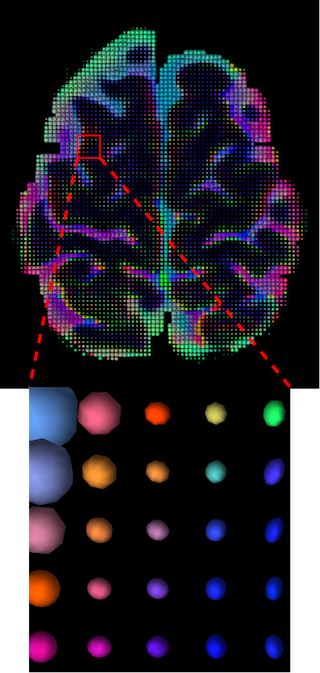

III-D Qualitative Results

The visualization of inpainted results (showing the whole diffusion tensor for each voxel) generated from different models are demonstrated in Figure 3, where the tensor is represented in RGB coding that colours red, green and blue represent diffusion in the x, y, and z axes respectively. One typical example of reconstruction in the disrupted ROIs has been zoomed for visualization. Compared to the ground truth, TW-BAG is able to generate more distinct orientations following the original distribution and intensity across sagittal, coronal and axial views, which could demonstrate water diffusivity (denoted by eigenvalues of tensor model) more accurately. As indicated in Figure 4, the boundaries and textures of the FA map for TW-BAG are less blurry than the other competing models, validating the effectiveness of TW-BAG from a neuroscience perspective.